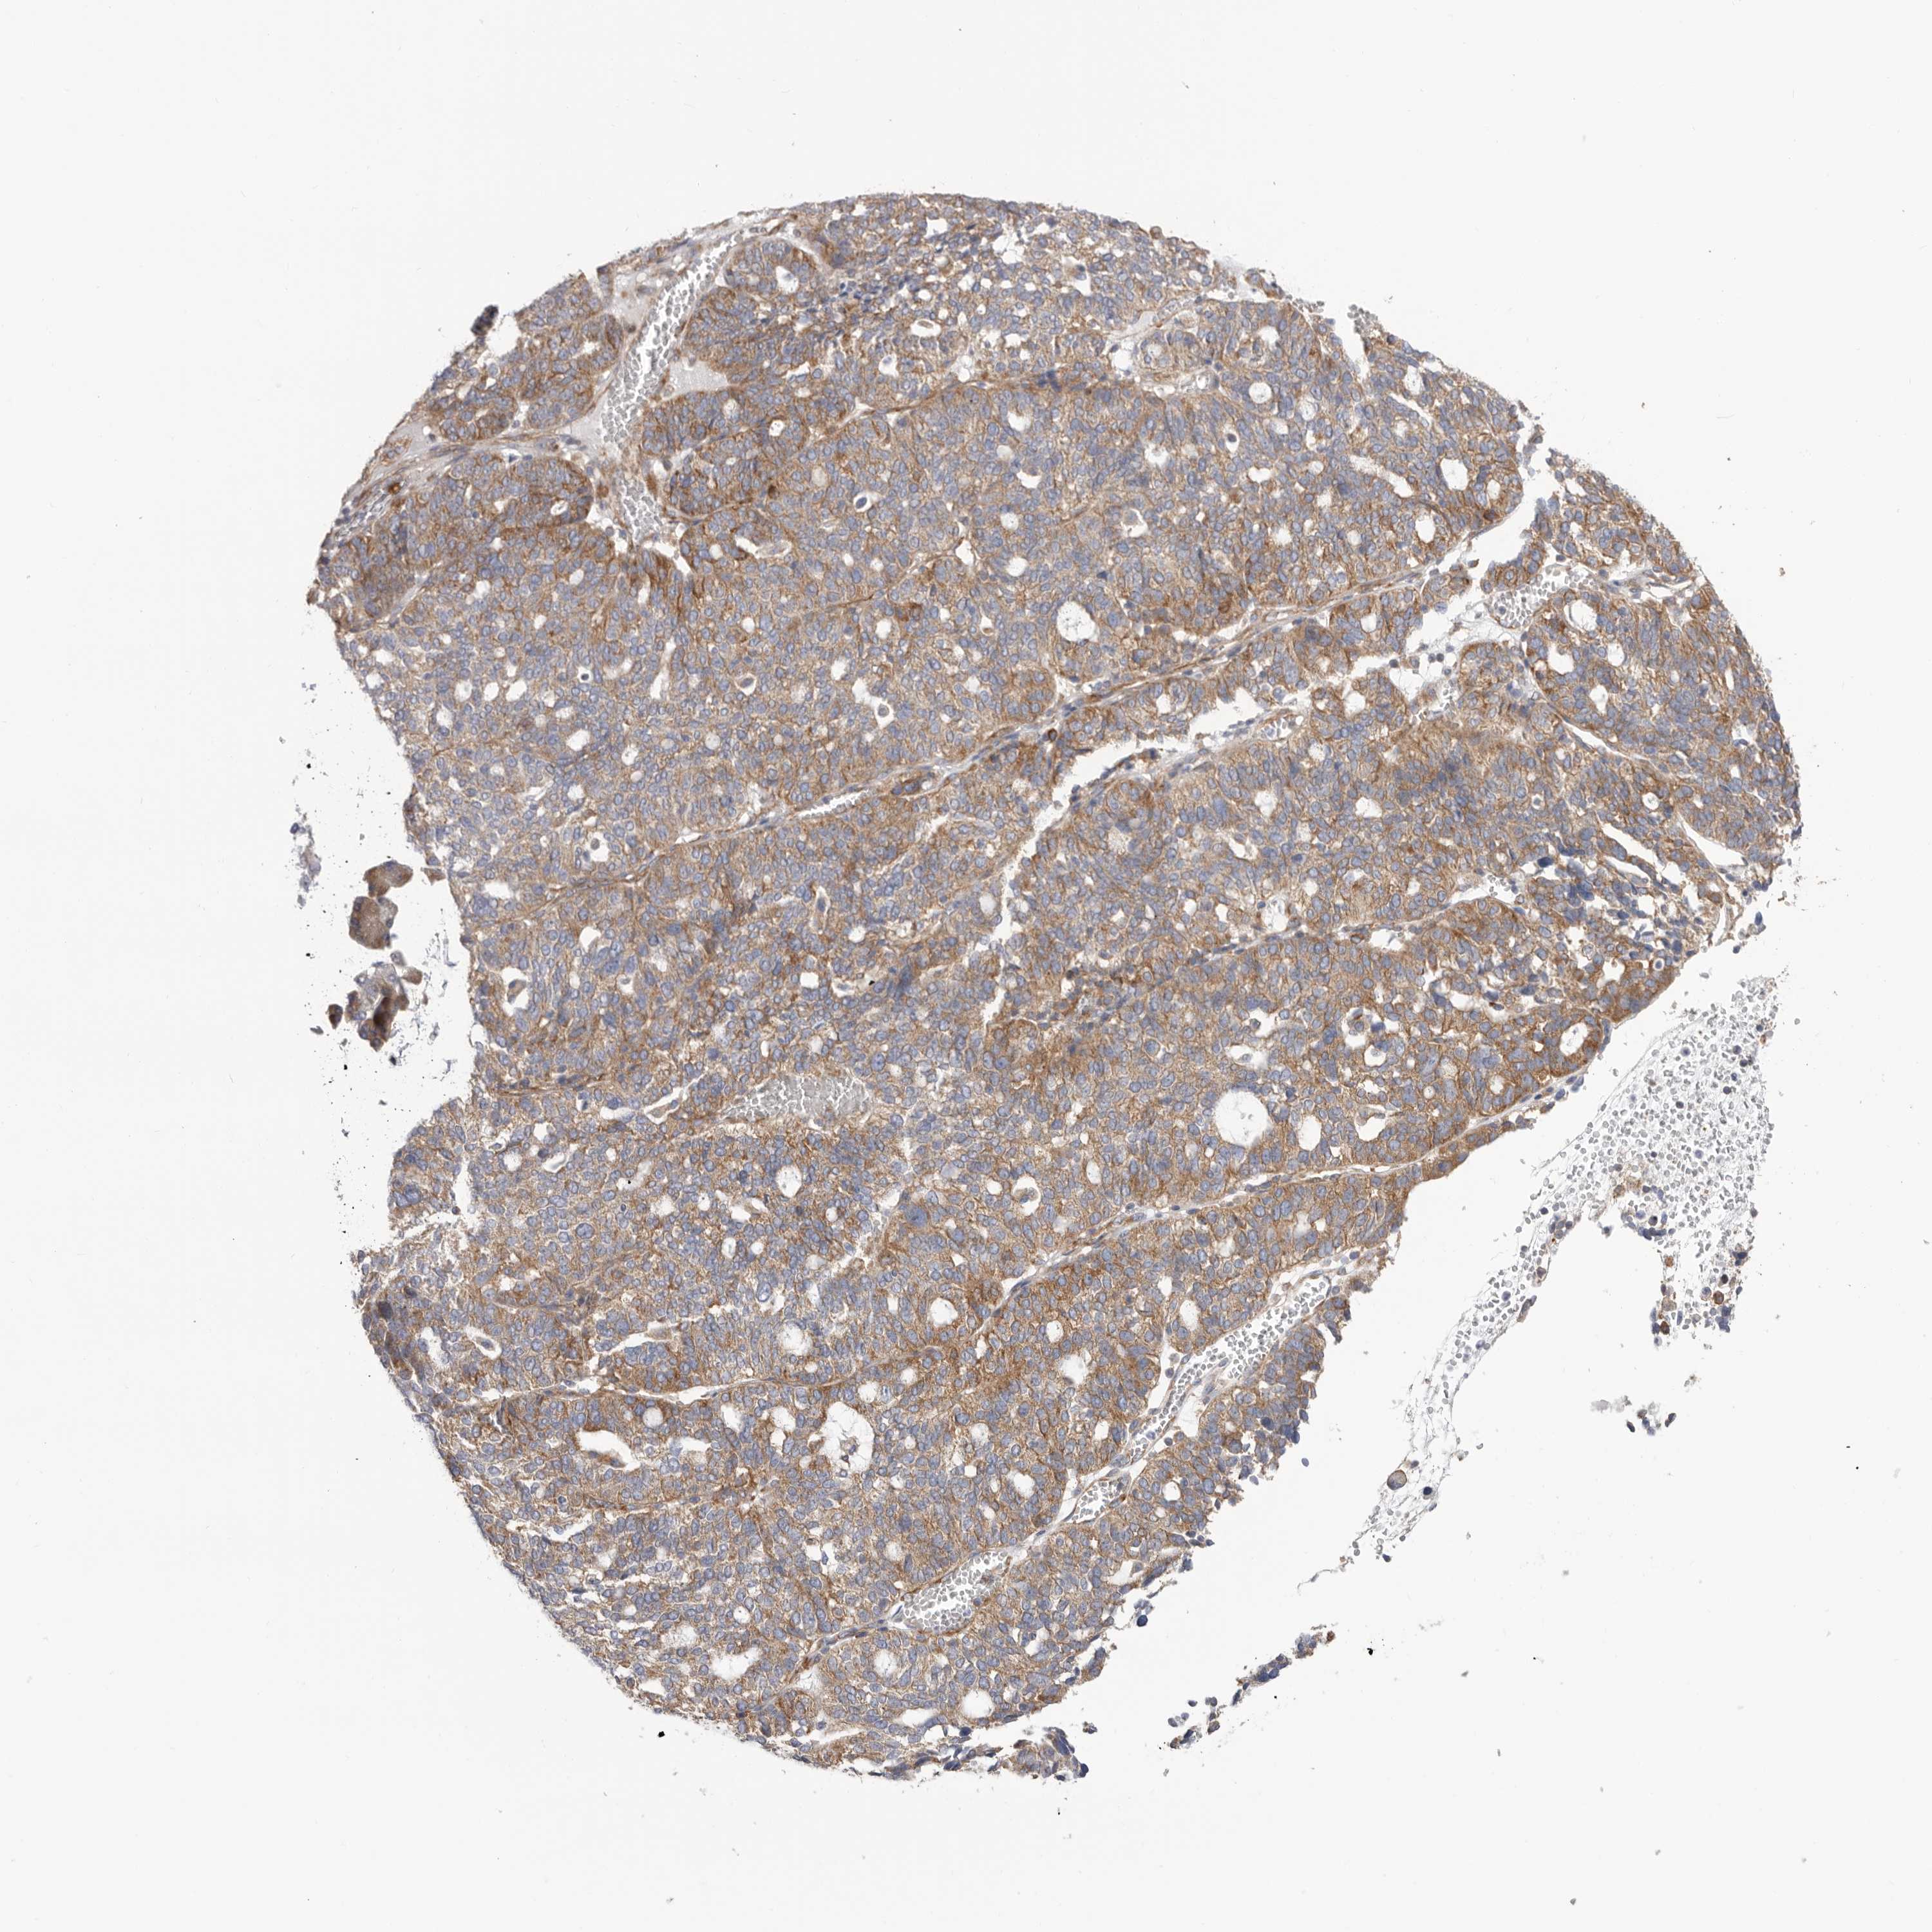

OVARIAN CANCER - Protein expressioni

A mouse-over function shows sample information and annotation data. Click on an image to view it in a full screen mode. Samples can be filtered based on level of antibody staining by selecting one or several of the following categories: high, medium, low and not detected. The assay and annotation is described here.

Note that samples used for immunohistochemistry by the Human Protein Atlas do not correspond to samples in the TCGA dataset.

Antibody stainingi

Antibody staining in the annotated cell types in the current human tissue is reported as not detected, low, medium, or high, based on conventional immunohistochemistry profiling in selected tissues. This score is based on the combination of the staining intensity and fraction of stained cells.

Each image is clickable and will lead to virtual microscopy that enables deeper exploration of all samples and also displays staining intensity scores, fraction scores and subcellular localization as well as patient and tissue information for each sample.

Antibody HPA020559

Antibody CAB026297

Cystadenocarcinoma, serous, NOS

Carcinoma, endometroid

Cystadenocarcinoma, mucinous, NOS

Carcinoma, NOS